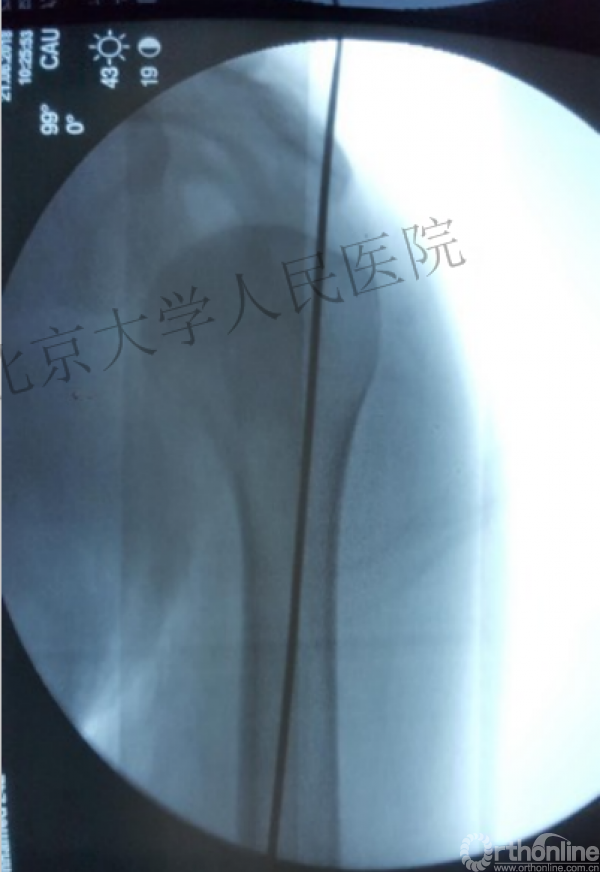

简单骨折的闭合复位技术:以克氏针作为“joystick”

髓内钉的应用复位是关键

复位良好的标准:颈干角:135°,大结节与肱骨头距离:8mm